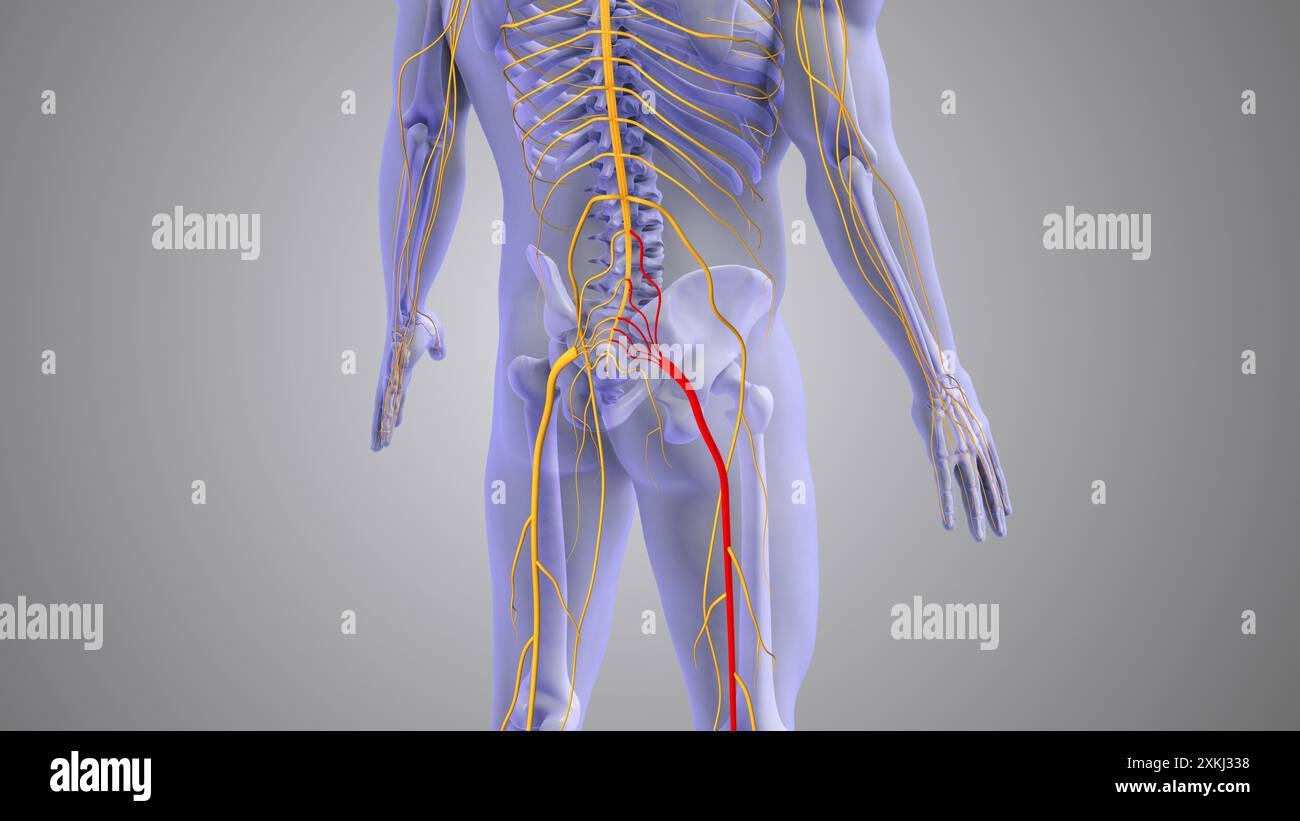

Conception médicale de la douleur du nerf sciatique Banque D'Imageshttps://www.alamyimages.fr/image-license-details/?v=1https://www.alamyimages.fr/conception-medicale-de-la-douleur-du-nerf-sciatique-image614438924.html

Conception médicale de la douleur du nerf sciatique Banque D'Imageshttps://www.alamyimages.fr/image-license-details/?v=1https://www.alamyimages.fr/conception-medicale-de-la-douleur-du-nerf-sciatique-image614438924.htmlRF2XKJ338–Conception médicale de la douleur du nerf sciatique